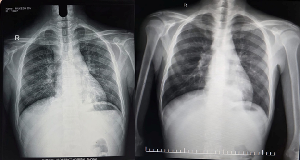

Chest X-ray showing bilateral lower zone opacities with ill-defined margins, consistent with consolidation. No obvious cavitation noted. Post treatment Chest Xray shows improvement.